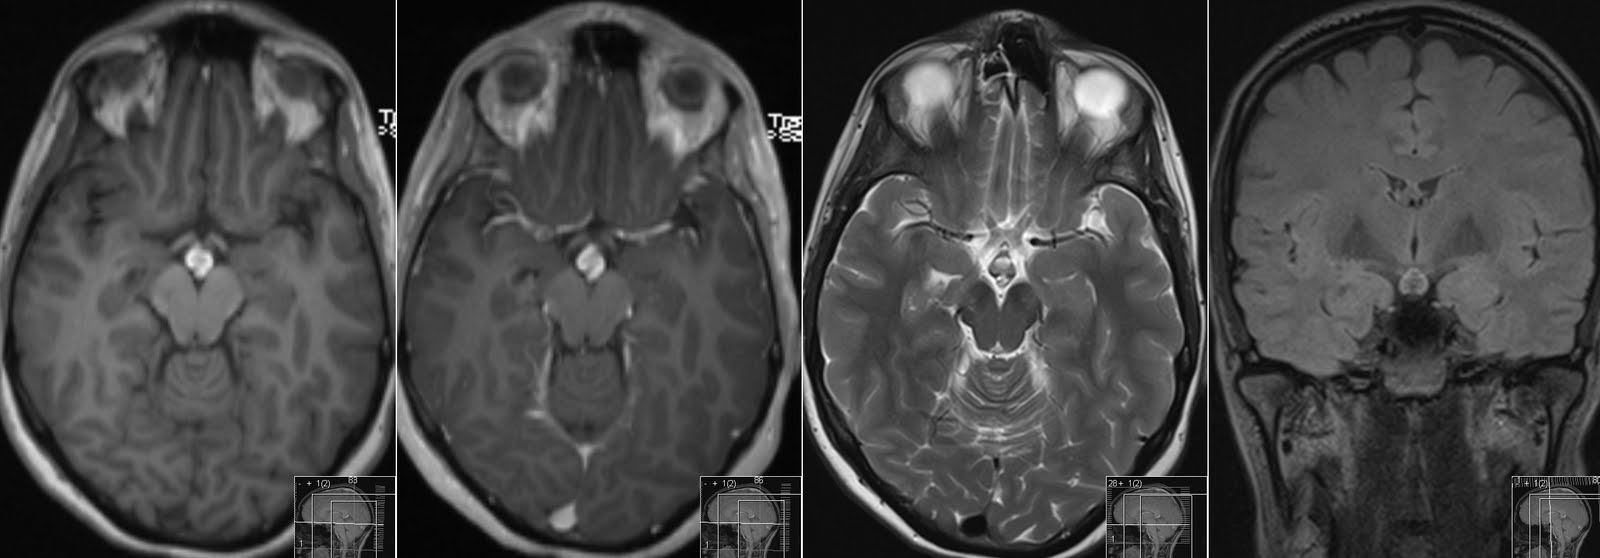

Мрт гито

Мрт гито 114 фото